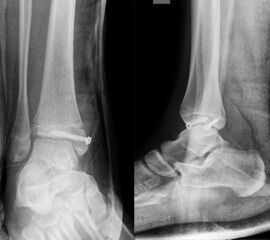

Übergangsfrakturen

Übergangsfrakturen sind spezielle Verletzungen, die ausschließlich in der Lebensphase beobachtet werden, in welcher die Wachstumsfugen teilweise geschlossen sind. Die Wachstumsfuge an der distalen Tibia schließt sich von ventromedial beginnend nach dorsal und lateral. Während die bereits geschlossene Wachstumsfuge eine hohe Stabilität aufweist, ist der knorpelige Anteil der noch offenen Fuge wesentlich weniger widerstandsfähig. Die mechanisch schwächste Schicht der Wachstumsfuge ist der Blasenknorpel. Durch Biege- und Scherkräfte kommt es zu einer Verletzung der Wachstumsfuge mit Aussprengung eines metaphysären Keils. Übergangsfrakturen sind „unvollendete“ Fugenschaftfrakturen bei welchen die bereits geschlossene Fuge ein Auslaufen der Frakturlinie durch die Fuge verhindert und daher die Bruchlinie ins Gelenk ausläuft (v. Laer 2013).

Rein epiphysäre Frakturen werden als Twoplane-Frakturen bezeichnet. Der Frakturverlauf liegt in der Epiphyse und dem noch nicht verknöcherten Anteil der Wachstumsfuge. Gibt es noch einen zusätzlichen metaphysären Keil handelt es sich um eine Triplane-Fraktur. Bei einer Triplane-Fraktur kann sich in Einzelfällen die metaphysäre Fraktur bis in die Epiphyse fortsetzen, sodass eine zusätzliche Querfraktur resultiert. Es entsteht der Eindruck eines zusätzlichen hinteren Volkmann Fragments.

In Abhängigkeit vom Reifezustand der Wachstumsfuge kann der epiphysäre Frakturspalt sehr weit medial bis ganz lateral zu liegen kommen. Ein sehr weit lateral liegender Frakturspalt entspricht funktionell nahezu einem knöchernen Ausriss der vorderen Syndesmose, was sich im Röntgenbild an einer erweiterten Malleolengabel erkennen lässt 9

Der teilweise komplexe Frakturverlauf bei Übergangsfrakturen lässt sich im CT zuverlässig darstellen 10. Der erfahrene Untersucher kann bereits mit Röntgenaufnahmen des Sprunggelenks in zwei Ebenen in Verbindung mit zwei 45° Schrägaufnahmen sehr umfassende Aussagen zum Frakturverlauf treffen (v. Laer 2013), die Präzision und Aussagekraft der Computertomografie ist aber zweifelsohne überlegen und wird von den meisten Behandlern bevorzugt 11, auch wenn sich zu diesem Thema in der Literatur eine teilweise sehr emotional geführte Diskussion findet. Einigkeit hinsichtlich der Indikation für ein Schnittbildverfahren besteht bei Triplane-Frakturen, wenn Zweifel darüber bestehen, inwieweit die metaphysäre Fraktur den tragenden Gelenkanteil tangiert 12.

THERAPIE

Übergangsfrakturen weisen häufig nur eine geringe Dislokation auf (Abb. 25). Möglicherweise wurden diese Verletzungen in ihrer Rolle hinsichtlich einer Arthroseentwicklung lange Zeit überbewertet 13. Nicht dislozierte Frakturen können konservativ behandelt werden.